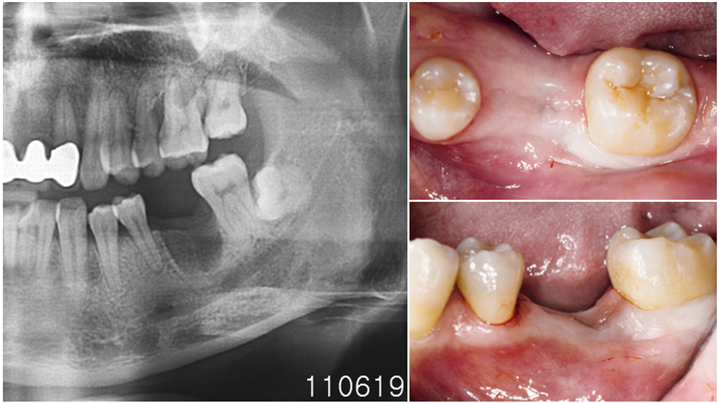

Clinical case: Bone filling into the bottom of deepest thread at 8.0mm AnyRidge fixture

- Courtesy of Dr. Kwang Bum Park -

Keywords

AnyRidge, Knifethread ,extraction socket, ,initial stability ,Allograft, ,osseointegratio ,Dr. Kwang Bum Park, , Mandibular, Single replacement, AnyRidge, Mega-oss,

Products used

Implant system-AnyRidge, Regeneration-Mega-Oss

“AnyRidge implant enables fast and stable

osseointegration at this extreme case of bone defect. ”